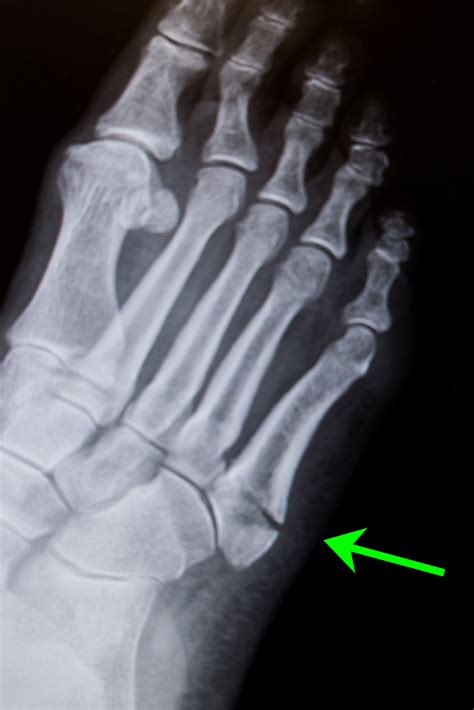

Diagnosing a Fifth Metatarsal Fracture

Diagnosing a Fifth Metatarsal Fracture typically involves a combination of physical examination and imaging tests. The diagnostic process may include:

• Physical Examination: A healthcare provider will examine the foot, checking for swelling, tenderness, and deformity.

• X-Rays: X-rays are the primary imaging tool used to confirm the presence and location of the fracture.

• CT Scans or MRIs: In some cases, more detailed imaging such as CT scans or MRIs may be required to assess the extent of the fracture and plan treatment.